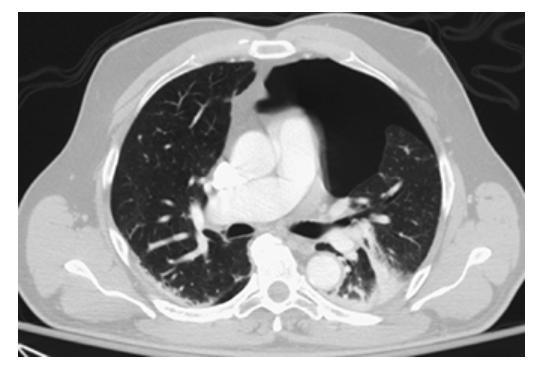

Pneumothorax. Axial CECT of the chest shows a large left pneumothorax as abnormal air density within the pleural space and a partially collapsed left lung.